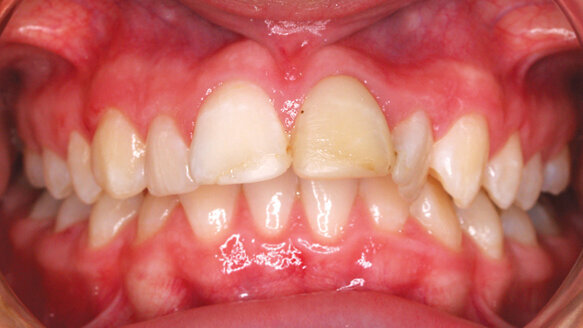

This 13-year-old girl’s profile (Fig. 1) shows a severely underdeveloped mandible, with a subsequent overbite. The strain of the mentalis muscle also betrays a “reverse swallow” with mentalis activity, which is the cause of this skeletal malocclusion.

After six months of myofunctional appliance use and myofunctional therapy, the release of muscle tension has allowed the mandible to translate anteriorly, with seemingly spontaneous lower dental alignment also a happy bonus (Fig. 2).